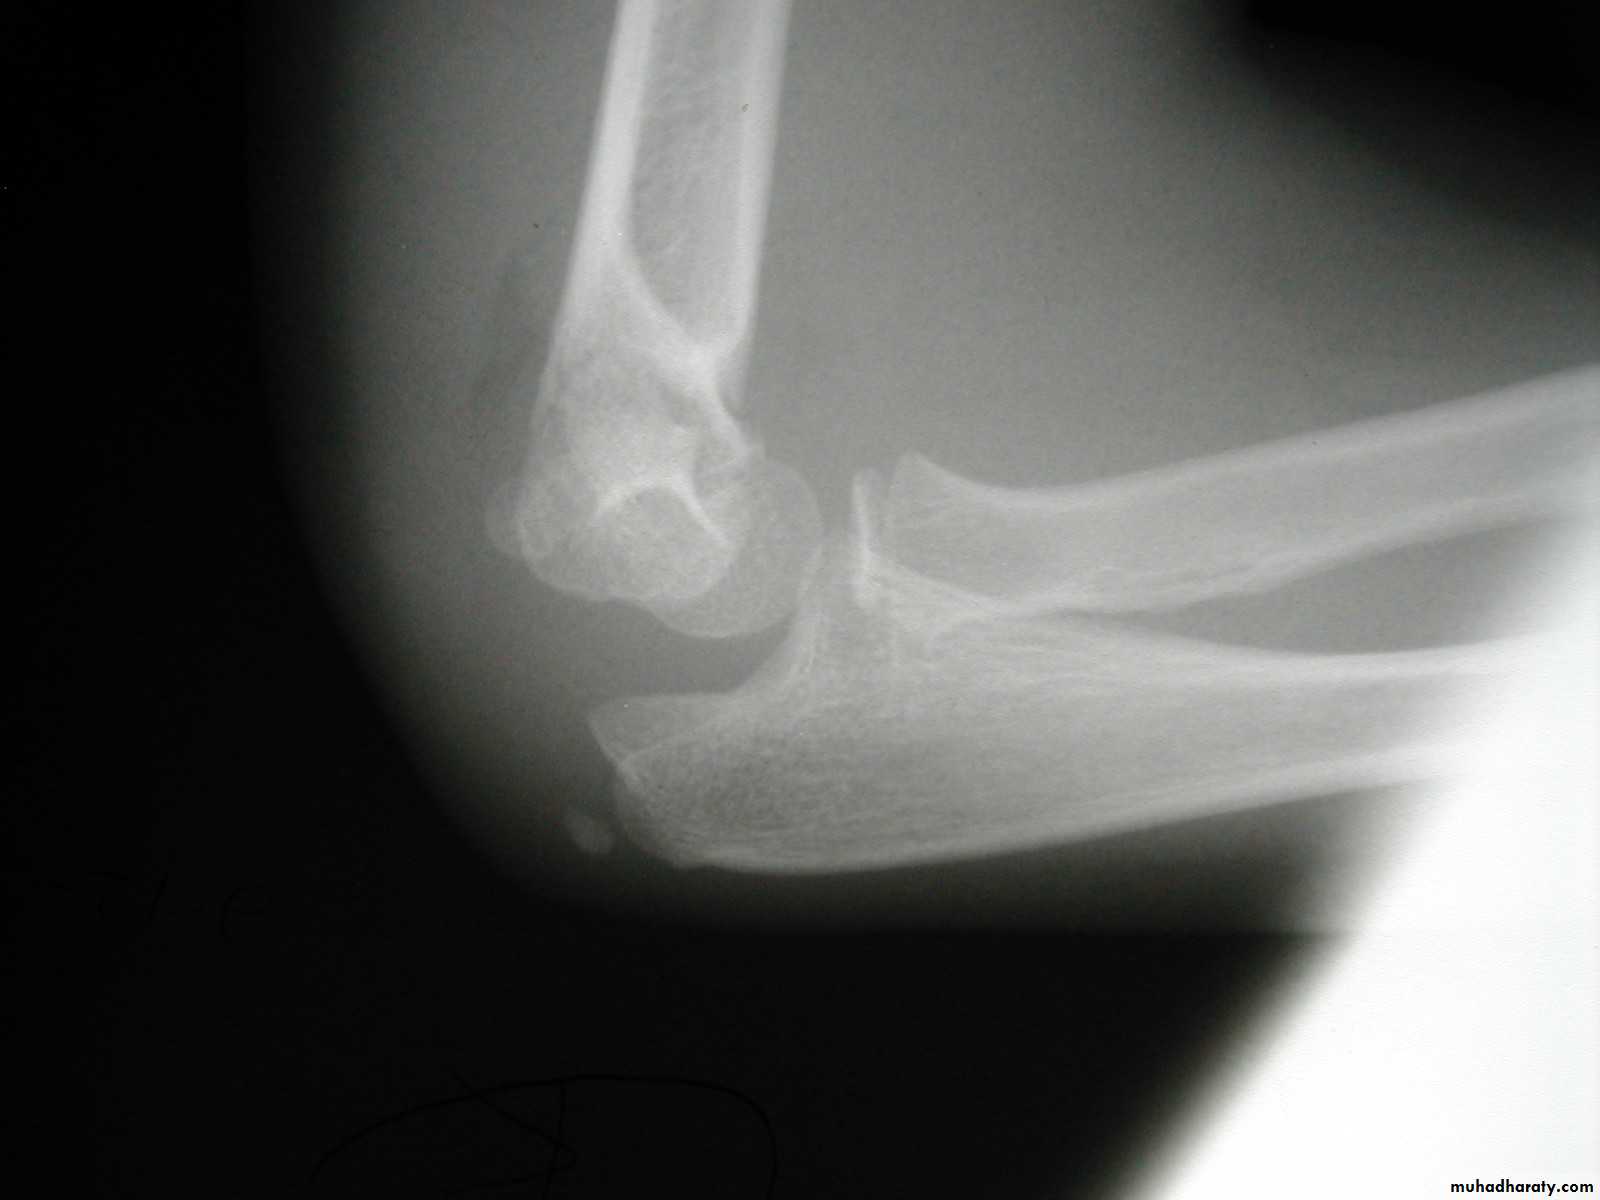

Five y.o. male with this fracture pattern

• Following obtaining a satisfactory closed reduction how do you propose to stabilize it?Multiple lateral pins

Stable ??Five y.o. male with this fracture pattern

• Following obtaining a satisfactory closed reduction how do you propose to stabilize it?

Medial-lateral

retrograde cross pinsDifficult and unstable